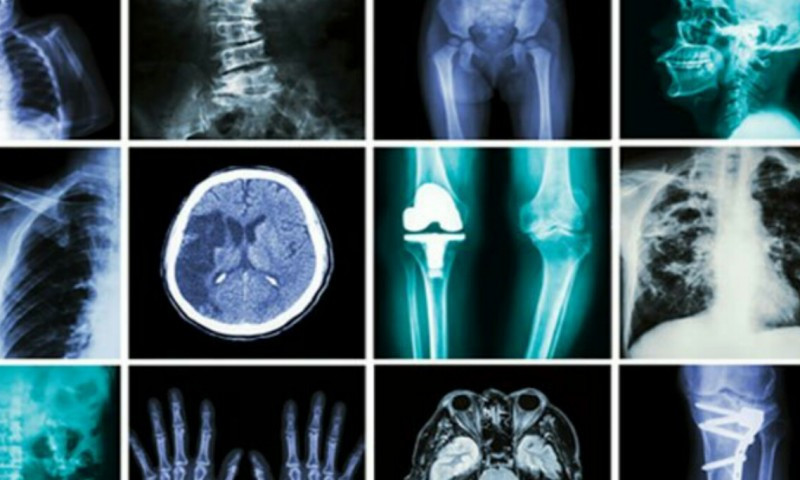

रेडियोलोजी अन्तर्गत विकिरणयुक्त एक्स–रे, फ्लुरोस्कोपी, म्यामोग्राम, सिटीस्क्यान तथा विकिरणरहित अल्ट्रासाउन्ड, एमआरआई लगायत प्रविधि पर्छन् ।